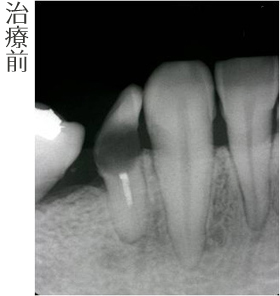

審美インプラント治療(こだわりのインプラント治療)右下小臼歯部

右下小臼歯部

虫歯が進行していたために抜歯となりました